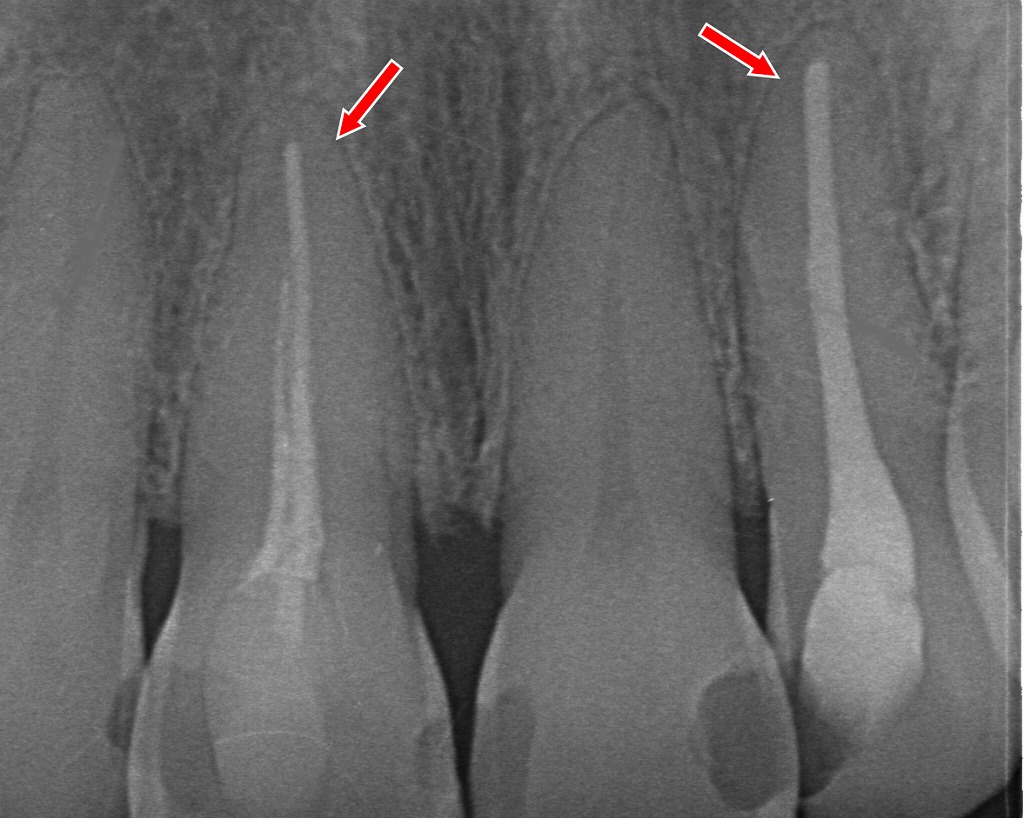

◆ 前歯の色の違いがはっきり分かる例

赤矢印の前歯は、周囲の歯よりも濃い黄色〜茶色に見えています。

これは神経を失った歯(失活歯)に起こりやすい変色で、歯の内部が徐々に濃い色へ変化するため、外側からも黄ばみとして目立ってきます。

神経がある健康な歯は、内部に水分が保たれており透明感がありますが、神経を取った歯は時間とともに乾燥・変性が進むため、全体が暗くくすんで見えるようになります。

レントゲン写真解説:

赤矢印の歯には、根の先端まで白い材料(根管充填材)が入っています。これは神経を取った処置(根管治療)を行った歯の証拠です。

神経を取ると、歯の内部は代謝が止まり、水分量が減り、時間とともに**色が濃くなる(黄ばみ・茶色化)**傾向があります。

レントゲンでは内部構造しか分かりませんが、実際の口腔内写真(1枚目)ではこうした変色として視覚的に現れます。